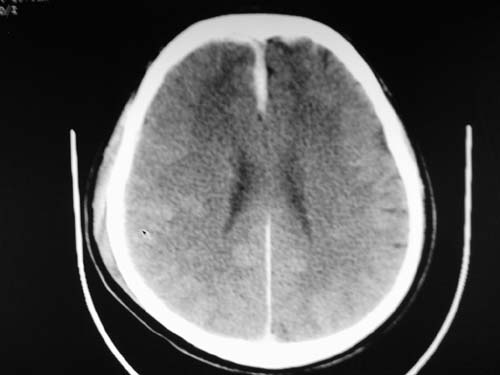

标题: CT17020:是硬膜下的吗?

脑中线内血肿,是硬膜下的吗?

脑中线内血肿——硬膜下血肿。

脑中线内血肿——硬膜下血肿。我们一般认为中线即可是硬膜下,也可是蛛网膜下腔的。边缘锐利,张力高的考虑硬膜下的,边缘模糊的,考虑下腔的。如果有老师有肯定的答案,麻烦下给我发个短信

支持镰旁硬膜下血肿,颅骨骨折,头皮损伤.

这个病人年龄不小吧,右侧脑沟不清,中线结构稍有左移,右侧额颞顶及右镰旁硬膜下血肿,另有蛛血,骨折。

外伤后引起的颅骨骨折、硬膜下血肿、皮下血肿,颅骨骨折引起的矢状窦破裂,形成大脑纵裂内血肿。